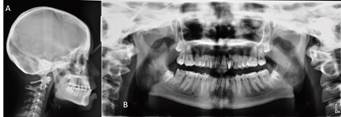

El diagnóstico integral con enfoque de riesgo es paciente género femenino, 16 años, potencialmente cooperadora, sin riesgo social, con riesgo biológico general, dentición permanente, gingivitis generalizada asociada a condición sistémica, lesión compatible con fibroma irritativo en flanco lingual izquierdo a nivel de 3.7. (Figura 2), caries oclusal profunda en diente 4.7, clase III esqueletal, biotipo braquifacial, perfil anterior anteinclinado, clase III canina y molar bilateral, overjet y overbite disminuidos, persistencia de dientes 5.3, 6.3 y 8.3, caninos permanentes con anomalía de tamaño por diente pequeño, apiñamiento dentario severo en maxilar y moderado en mandíbula, líneas medias dentarias no coincidentes, dinámica mandibular normal, respiración mixta, incompetencia labial, anteposición de cabeza. Se determinó la persistencia de tres caninos temporales, pero debido a la alteración de forma de los caninos definitivos se cuantificó éstos últimos como supernumerarios (Figura 3).

Los objetivos generales del tratamiento incluyeron: Adaptación e integración sensorial, prevención y refuerzo al huésped, tratamiento periodontal, rehabilitación de diente 3.7, exéresis y biopsia de lesión lingual y tratamiento de ortodoncia. Los objetivos iniciales del tratamiento de ortodoncia fueron mejorar el perfil de clase III esqueletal, alinear y nivelar dientes superiores e inferiores, corregir Overjet y Overbite disminuidos, obtener neutroclusión canina bilateral, mantener la salud de la articulación temporomandibular, restablecer salud periodontal y dentaria y recuperar la función lingual alterada a través de trabajo fonoaudiológico.